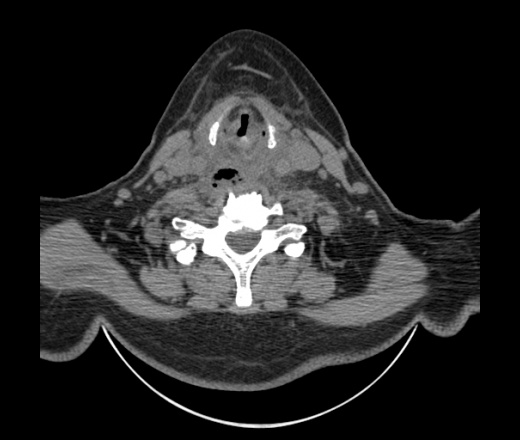

Женщина поступила в х/о спустя 4 дня после того как при употреблении карася подавилась костью.

Наличие газа в средостении на протяжении тел С2-С6 (медиастинальна эмфизема); рыбная кость на уровне тела С6.

При всем уважении, но говорить о медиастинальной эмфиземе, оценивая мягкие ткани шеи, как-то слишком резко. На мой взгляд, это ретрофарингеальное пространство.

Эвакуировали почти 100мл гноя. Но кость не смогли найти. Думаю что она даст дальнейшее ослоднение. Эндоскопически за черпалонадгортаной звязкой не смогли зайти в пищевод, все мягкие ткани отечные, просвет пищевода сдавлен. По всей видимости параэзофагеальная клетчака тоже задействована. Эмпиема, если ее можно так назвать, незнаю как правильно дошла до уровня яремной вырезки. Чем закончиться напишу. Ждем медиастинита.

Согласен с Вами; конечно, наличие газа в клетчатке ретрофарингеального пространства (затмение с опечаткой..). К сожалению, процесс "продвигается" к медиастиниту. Но почему никто, не отмечает наличие рыб. кости; или это для Всех очевидно?

Кость то мы сразу выявили, размеры где то 17*2мм, но ее так и не получается найти в этой каше